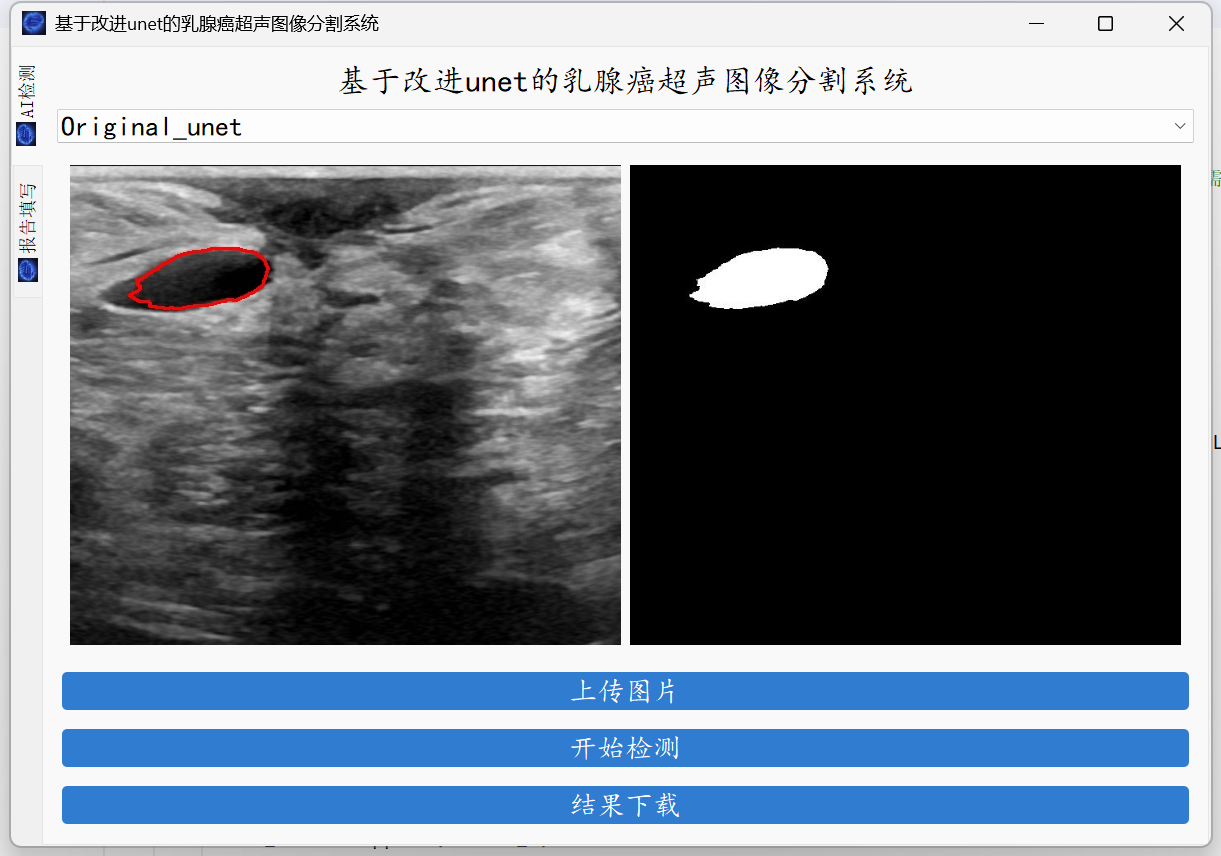

大家好,这里是肆十二!本次,我们为大家带来的是乳腺超神图像分割。深度学习技术的应用不仅提高了乳腺超神图像分割的精度和效率,也为医学影像分析带来了智能化的转变。借助人工智能,医生可以获得更多维度的辅助信息,从而做出更为精准的临床决策,推动了医学领域,尤其是在乳腺超神疾病的早期筛查、诊断和治疗方面的发展。在这期的教程中,我们将会教会大家如何使用服务器训练我们的乳腺超神图像分割模型以及将我们云端训练好的模型应用到本地的电脑上,最终实现的效果如下。

图形化界面封装

最后就是图形化界面的封装了,这里我们使用了pyqt的技术。

系统支持医学图像的分割、轮廓的查找以及简单的病例的记录。